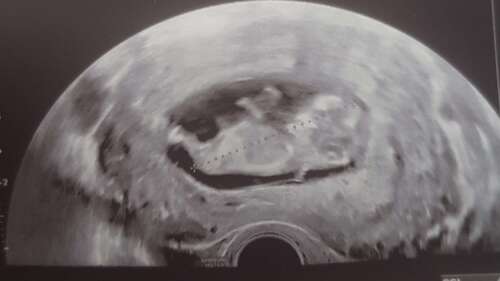

Endlich ein Herzschlag & 2 stolze CM groß bei 8+4

Wir haben heute ein neues bekommen, bei 10+4, sehen unsere erbse aber in 2 Wochen schon zum nipt wieder 🥰🥰 kann es kaum erwarten 🥰🥳

Unser Wunder heute bei 12+2 ☺️

12+1 :) von heute